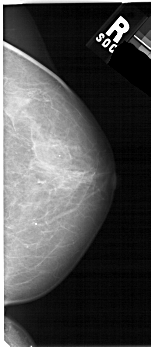

Digital Database for Screening Mammography

Volume: benign_07 Case: A-1686-1

A_1686_1.LEFT_MLO

LEFT_MLO LINES 5491 PIXELS_PER_LINE 2701 BITS_PER_PIXEL 12 RESOLUTION 43.5 OVERLAY

FILE: A_1686_1.LEFT_MLO.OVERLAY

TOTAL_ABNORMALITIES 1

ABNORMALITY 1

LESION_TYPE MASS SHAPE IRREGULAR MARGINS ILL_DEFINED

ASSESSMENT 4

SUBTLETY 3

PATHOLOGY BENIGN

TOTAL_OUTLINES 1

BOUNDARY